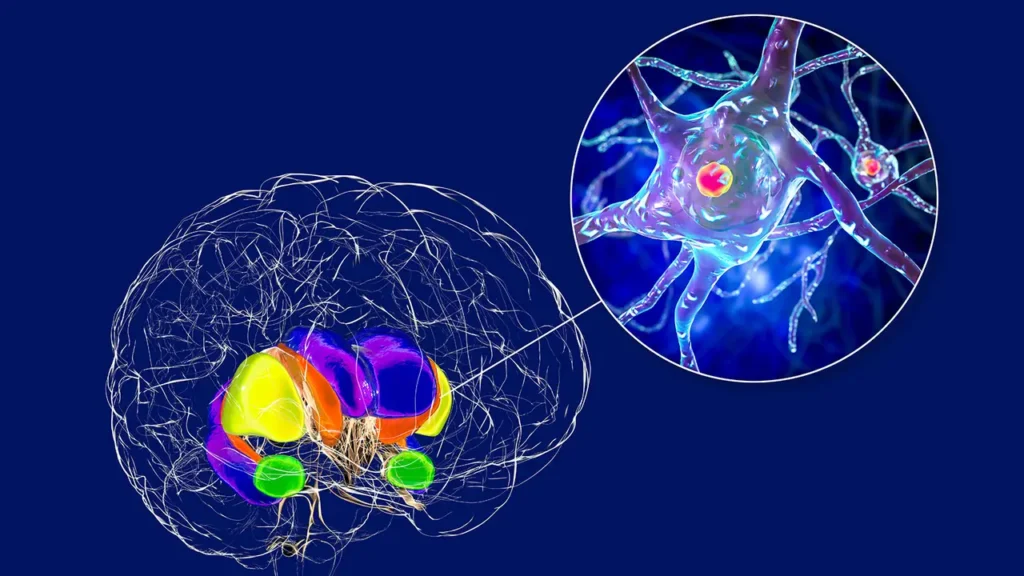

La mutazione riguarda il gene HTT, che codifica per la proteina huntingtina. Nella sua forma alterata, questa proteina subisce variazioni strutturali tali da diventare tossica per i neuroni, provocando danni progressivi e irreversibili al sistema nervoso centrale.

Il farmaco è stato iniettato direttamente in aree cerebrali profondamente coinvolte dalla patologia, come nucleo caudato e putamen, utilizzando una tecnica stereotassica guidata da risonanza magnetica. L’operazione, complessa e di lunga durata, richiede tra le 12 e le 18 ore di tempo.